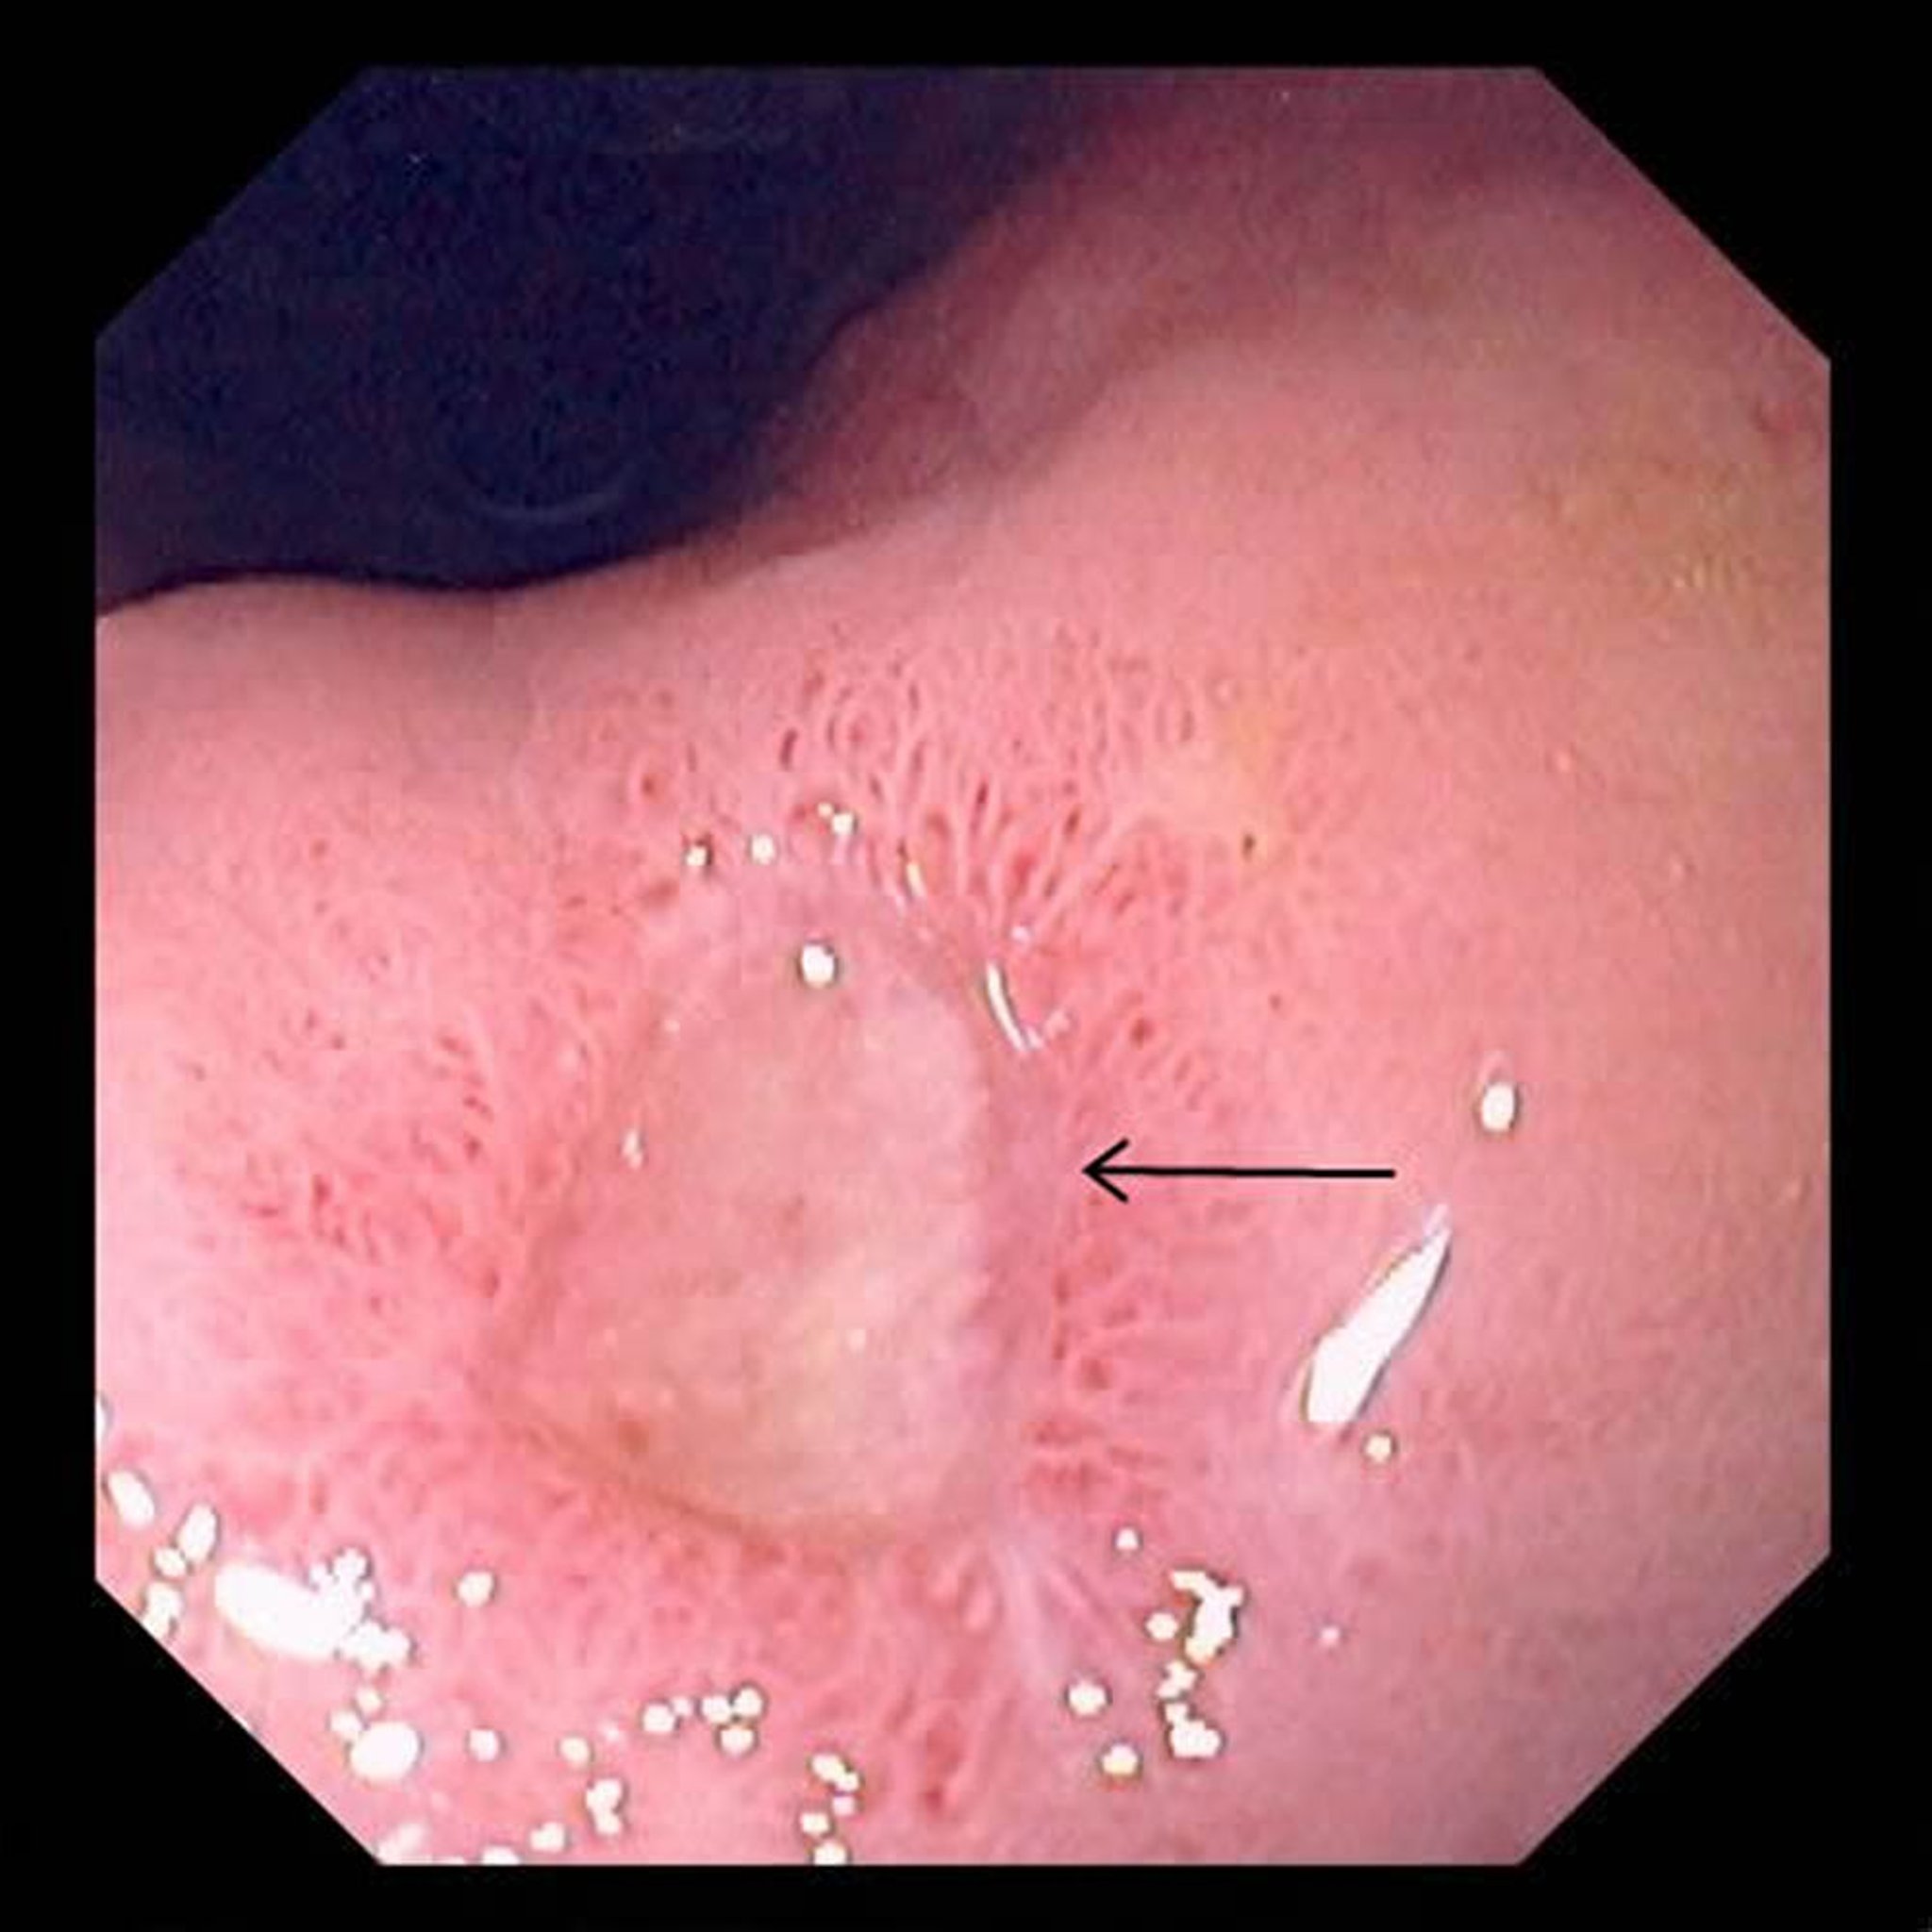

画像

胃潰瘍

いかいよう

この

写真

しゃしん

には、

胃

い

の

大

おお

きな

潰瘍

かいよう

(

矢印

やじるし

)が

写

うつ

っています。

Photo provided by David M.Martin, MD.